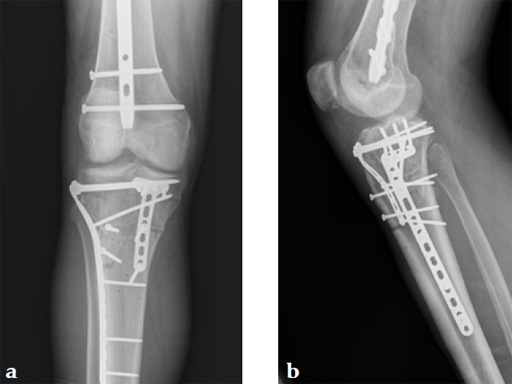

The patient returned to the operating room once soft tissue allowed for open reduction and internal fixation of the tibial plateau fracture via a lateral utility and anteromedial approach. Placement of low bend 3.5 mm proximal tibia plate laterally and 3.5 mm locking T-plate anteromedially to buttress the impacted anterior rim (Fig 4, Fig 5).